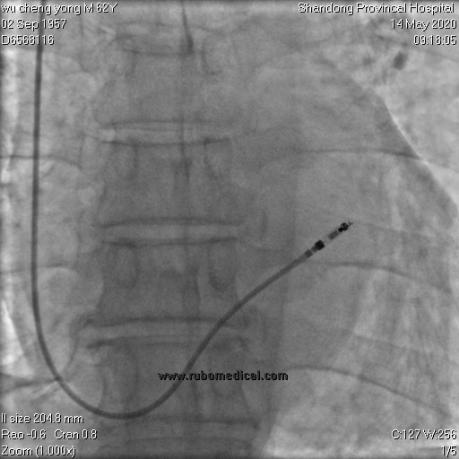

右心室主动电极植入后

右前斜以及左前斜位影像